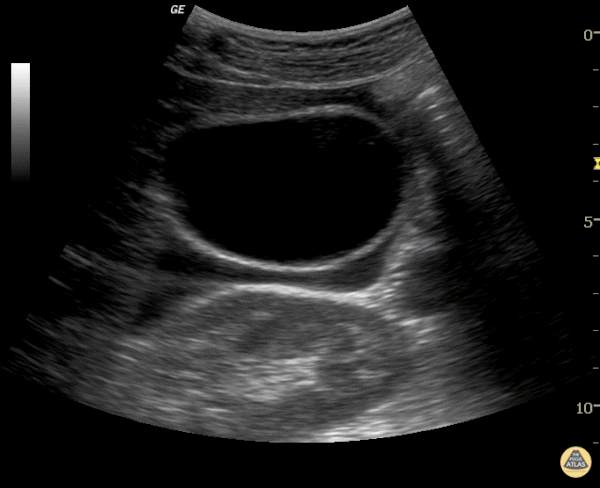

Biliary - Free Fluid around Normal Gallbladder

There is a lot of pericholecystic fluid surrounding this gallbladder but no other signs of inflammation. The gallbladder wall is normal, there are no stones, and there is no sonographic Murphy's sign. The free fluid is likely from another source, not acute cholecystitis. Justin Bowra MBBS, FACEM, CCPU Emergency Physician, RNSH et al.